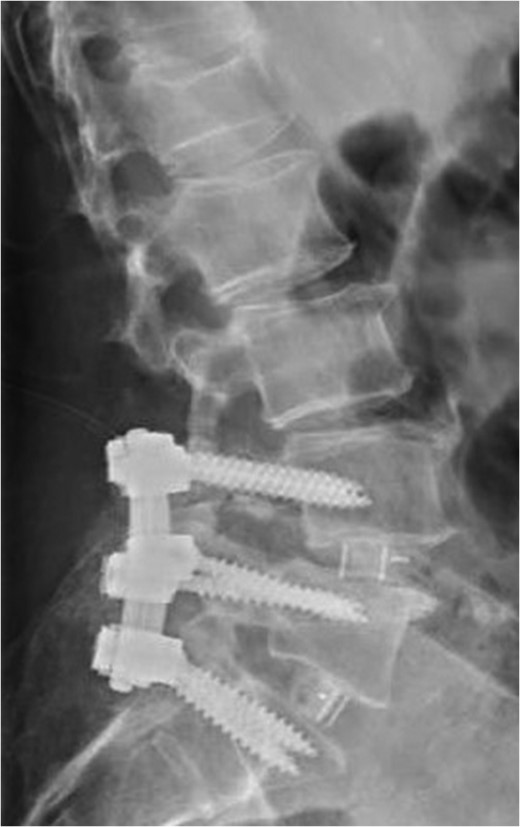

Standing neutral lateral lumbar radiograph obtained 17 months following the patient's L3–S1 laminectomy. The patient is now dealing with a Grade 1 anterolisthesis of L4 on L5, with a mild degree of retrolisthesis at each of the cranial levels depicted.